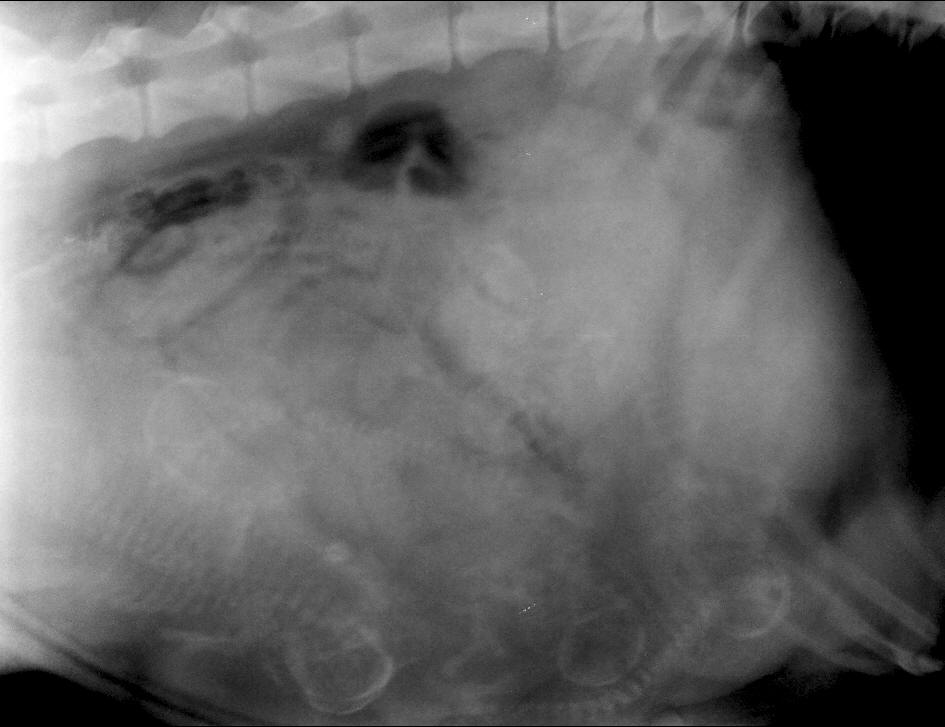

<-- La radio permet de compter les chiots à naître